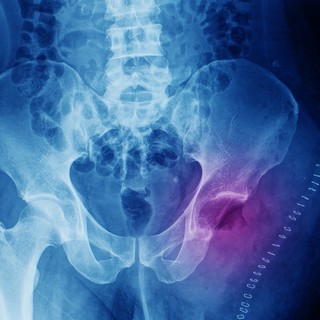

Röntgenvizsgálattal a következő látható. A jól differenciált, lassabban növő kondroszarkómára az jellemző általában, hogy centrálisan, vagyis csonton belül keletkeznek. A csontot felfúvó, lebenyes elváltozást hoznak létre.

A tumorban rendszerint eltérő mértékű mészlerakódások vannak. A csont felszínéről kiinduló kondroszarkóma a lágyrészek fele növekszik, későbbi stádiumban pedig már összefüggően, elmosódó képet ad. CT és MR képalkotó vizsgálat segít a lágyrész érintettség felderítésében és a műtét megtervezésében is. A biztos diagnózishoz szövettani mintavételt (biopsziát) kell végezni.